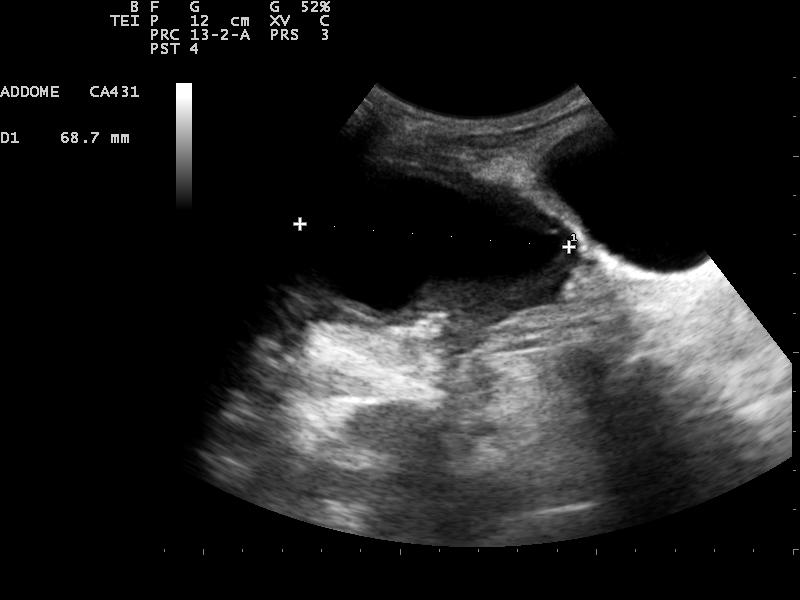

Il bambino viene sottoposto ad un�ulteriore ecografia addominale (Figura 2) che mostra la presenza di una formazione ovalare a parete spessa in sede sopravescicale, compatibile con una raccolta saccata e nella quale si riconosce l�estremit� distale della derivazione ventricolo-peritoneale.

Figura 2. Ecografia: formazione ovalare anecogena a parete spessa, in sede paramediana destra sovravescicale.